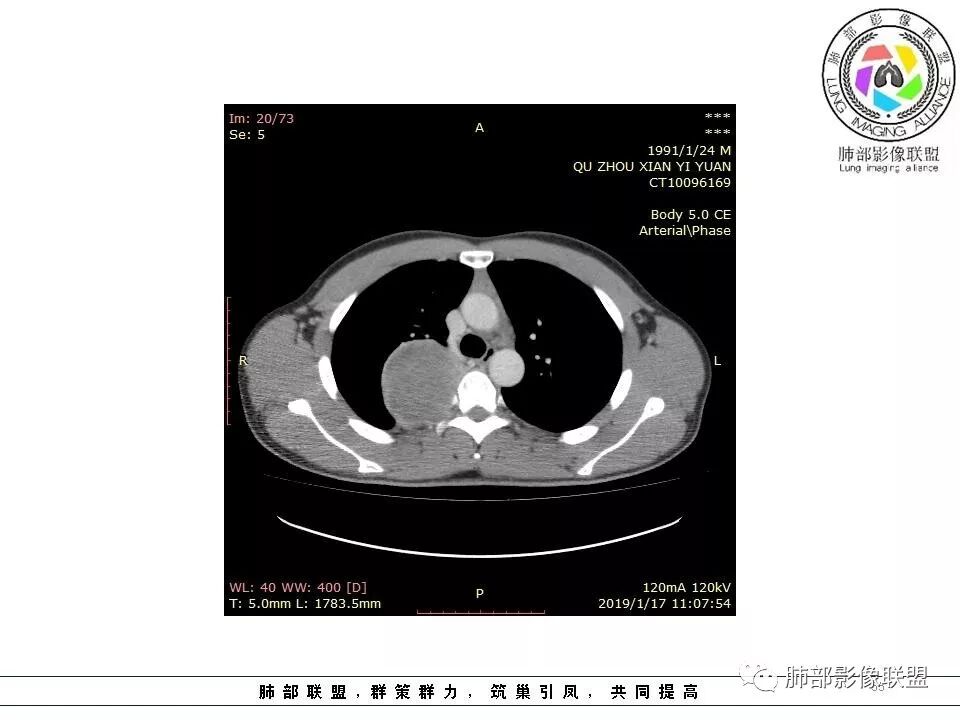

右后纵膈脊柱旁软组织占位,形态规则类圆,边缘光整,肺组织受压,胸膜尾,肋间动脉供血。中度不均匀延迟强化。

右后纵膈脊柱旁软组织占位,边界清晰,光整,肺组织受压。胸膜被掀起,肋间动脉供血,中度不均匀延迟强化。考虑神经鞘瘤,不除外纤维瘤

右后纵膈脊柱旁软组织影,与纵隔结构分界不清,形态规则类圆,边缘光整,肺组织受压,胸膜尾,肋间动脉供血。肺动脉推移,中度不均匀延迟强化。考虑神经来源,神经鞘瘤,神经纤维瘤二者不易鉴别。

青年男性,间断胸痛;右侧脊柱旁可见一类圆形软组织密度影,密度欠均匀,增强扫描呈轻中度持续强化,邻近肺组织及肺动脉推移,可见肋间动脉供血,部分胸膜下脂肪可见,部分层面似见与右侧椎间孔相连。考虑后纵隔神经源性肿瘤。

青年男性,右侧脊柱旁软组织肿块,边缘膨隆,密度不均,临近肺组织受压、胸膜增厚,增强后动脉期呈不均匀强化,并可见肋间动脉供血,延迟期强化较均匀,定位肺外,首先考虑SFT,神经源性肿瘤待排

右肺占位,跨越上叶后段、下叶背,边缘光滑,瘤肺界面清,见肺压缩缘(线样不张`强化),见胸膜尾征,胸膜下脂肪未见明显增厚,肋骨丶脊柱未见侵袭及受压,渐进性丶地图样强化,冠状位似见体循环供血

诊断:SFT(来源壁层胸膜?一般小于20%)

1.右上胸内脊柱旁类圆形肿块,质地似乎比较坚实,密度稍显不均,但未显示明确的坏死。

2.肋间动脉病供血也提示肿块来自后纵隔?

3.相邻椎间孔未见扩大,也未见块影延入椎管,易起自于神经根的鞘瘤似乎找不到支持点。

4.静脉期轻度不均匀强化,注意不是环形强化,亦未见明确的“AB区”,这点也不支持神经鞘瘤。临床及病灶轻度强化都不支持副节瘤。